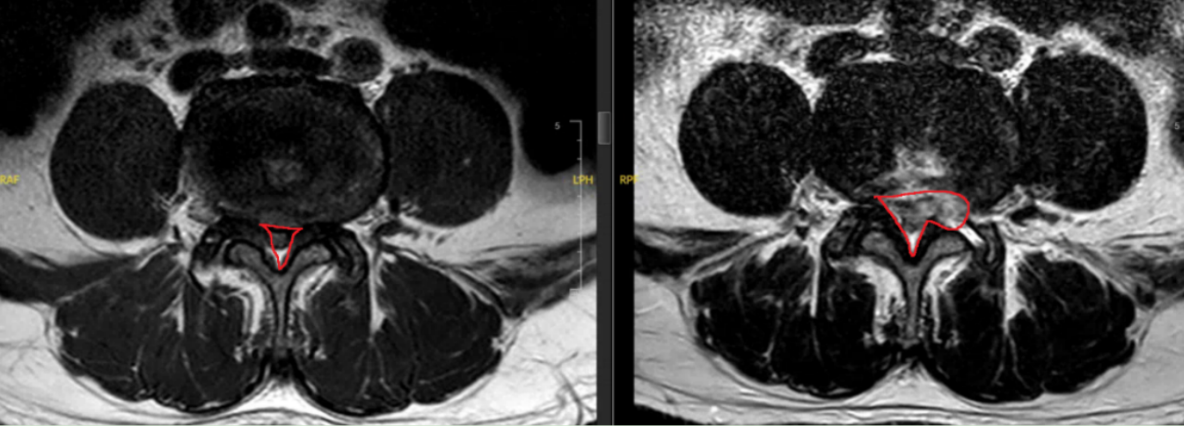

接诊后,胡旭民副教授带领团队结合何先生的病史、体征和影像学检查等,明确诊断其为“腰椎管狭窄症”。

6月9日上午,在排除手术禁忌症后,高粱斌教授、胡旭民副教授团队在局部麻醉下为何爷爷实施了微创椎间孔镜手术。术中取出大量导致压迫的病变增组织后,手术台上何爷爷双大腿及小腿麻木症状明显缓解,手术切口仅有1厘米。手术耗时1.5小时,术中何先生全程可以清醒地与医生进行交流。